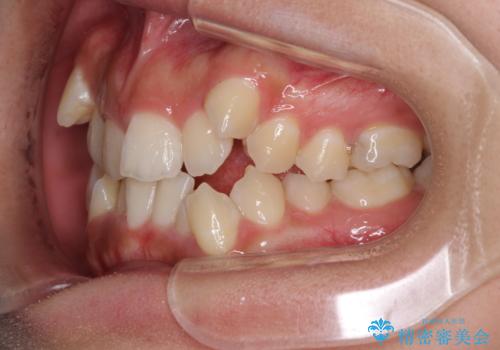

著しい八重歯が気になる インビザラインでの矯正治療

- 顕著な八重歯が気になるとのことで来院された患者様です。

インビザラインでの治療を希望されましたが、インビザライン単独では困難と判断されたため、補助装置や一部ワイヤー装置を用いて行うこととしました。

叢生が強いため、上下左右第一小臼歯4本を抜歯することとしました。